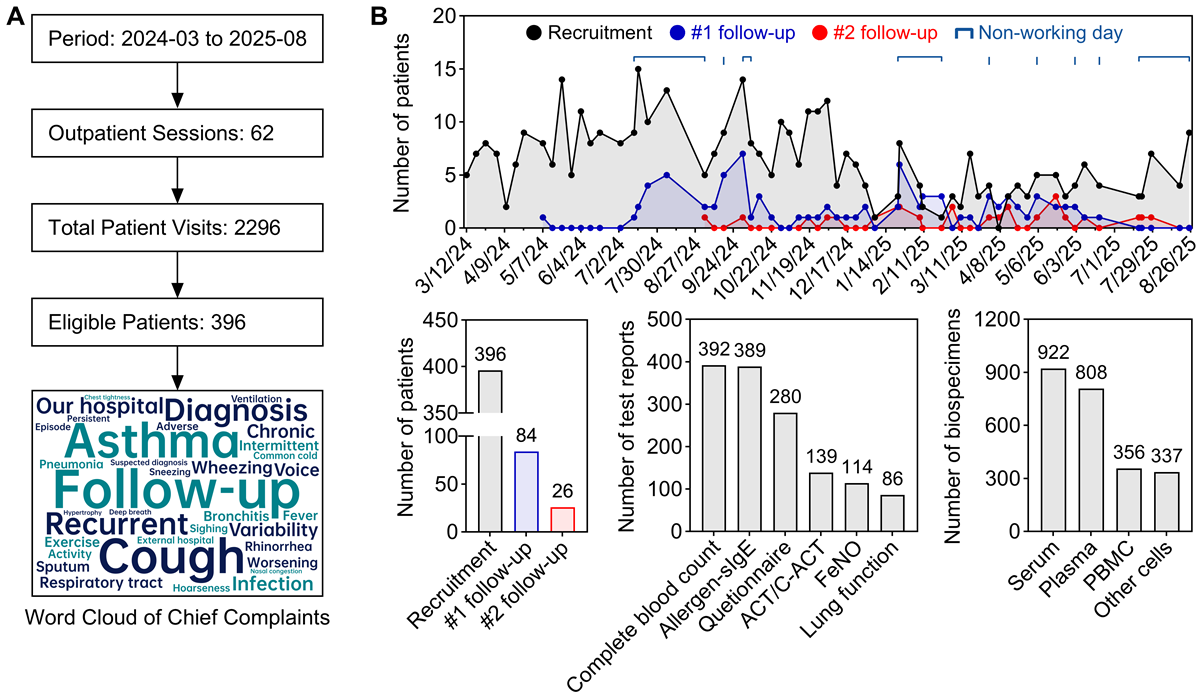

Between March 2024 and August 2025 (A), we organized 62 weekly outpatient sessions, evaluating an average of 37 patients per session (total 2296 visits; mean consultation time: 7.3 minutes). From this population, 396 eligible patients were enrolled (enrollment rate: 17.2%). Initial and second follow-up assessments were completed by 26.7% (84/315) of eligible patients at the first time point and 43.3% (26/60) of those eligible for the second follow-up, respectively (B). Temporal patterns indicated that follow-up completion rates peaked during school vacations and national holidays, reaching 1.4 times the baseline. These results demonstrate the feasibility of implementing a comprehensive research framework within the constraints of a high-throughput pediatric clinic, and underscore the need for flexible, family-centered follow-up strategies in real-world studies.

The integrated data and biospecimen repository constitutes a core output of the CRCA study. All enrolled children have standardized EMRs, which include 392 complete blood count reports, 389 allergen-sIgE reports, 86 lung function tests, 114 FeNO measurements, 280 parental questionnaires, and 139 ACT or C-ACT assessments. Furthermore, the biorepository has accumulated 2423 residual biospecimens (B), with coverage rates as follows: serum samples from 357 (90.2%) children, plasma from 317 (80.1%), PBMCs from 171 (43.2%), and other blood cell samples from 327 (82.6%), yielding an average coverage of 74.0% across these specimen types. The rate of hemolysis occurrence was 4.0% (16/396). These coverage rates meet the prespecified feasibility indicators for the biorepository component of the study.